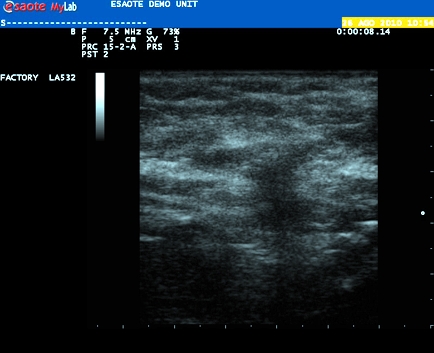

Età paziente: M 12 anni

Motivazione dell'esame: tumefazione dura, non dolente all'avambraccio destro, riscontrata da alcune settimane.

IL MIO REFERTO

In collaborazione: Dr. Aldo Tiberi - Ancona

Presentazione: Dr. Massimo Dolciotti - Ancona

Elaborazione digitale: Andrea Dini - Ancona

VISUALIZZA IL VIDEO